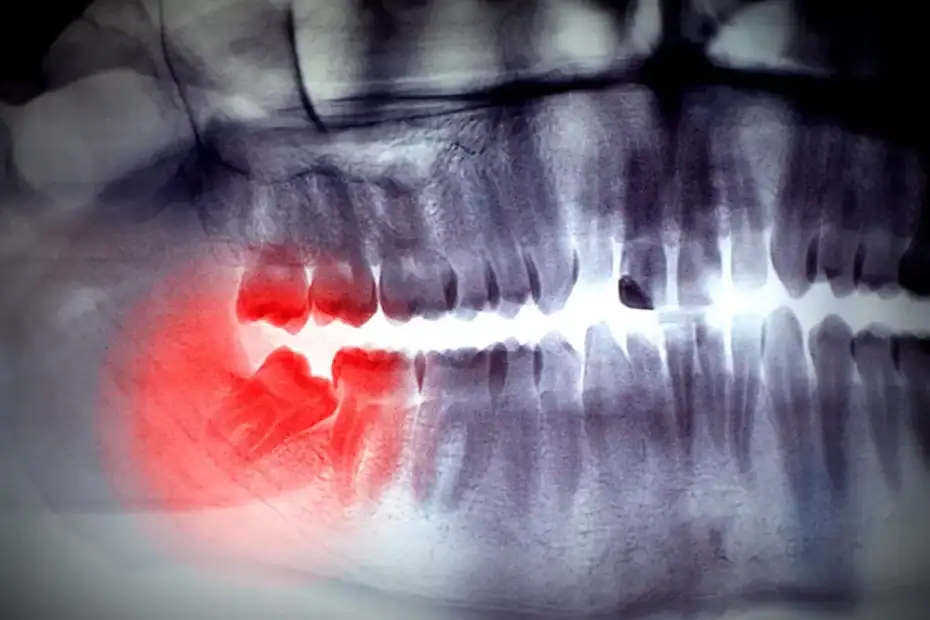

Smart ways to handle impacted wisdom teeth

There’s no fixed age that determines when to remove wisdom teeth, but leaving them in too long can lead to serious problems down the road.